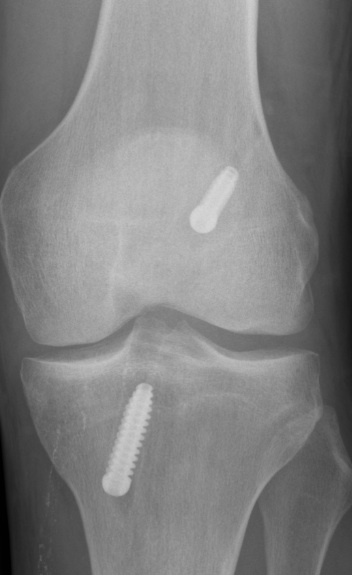

Uncertain if endobutton has flipped

- check with II

- cut down on lateral femoral cortex

- supplement with interference screw